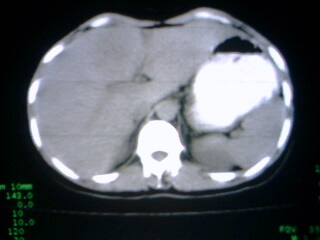

标题: CT9794:女 35Y 近两个月腹痛纳差明显消瘦 [打印本页]

标题: CT9794:女 35Y 近两个月腹痛纳差明显消瘦

在上几个层面肝脏有被病灶撑开的征像,病灶应该还是在肝上的,那就要考虑个猛的了,患然挺年轻,但对不住了,考虑肝癌

病人应该没有肝硬化病史,考虑胆囊癌可能性大,建议增强扫描除外肝腺瘤\\fnh等良性病变.

病变来自胆囊可能性大

增强,查afp。病灶象在肝内,若在胆囊内,肝内外胆管应有明显改变。

右肝癌。

巨大肿块。